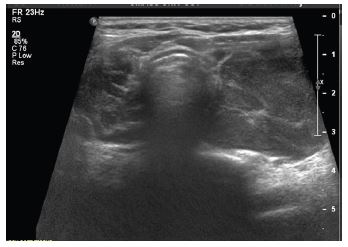

End of treatment PET scan revealed significant treatment response however there was evidence of residual asymmetric intense FDG uptake in the left thyroid gland (Figure 4). It was uncertain whether the PET findings represented inflammation due to Hashimoto’s thyroiditis versus residual lymphoma. Repeat biopsy of the left lobe showed patchy inflammatory infiltrate that may have been secondary to Hashimoto’s thyroiditis with no clear evidence of lymphoma (Figure 5). Due to the paucity of malignant cells in cases of TCHRBCL, residual lymphoma could not be excluded. Repeat PET scan 12 months later showed increase in size and uptake in her left thyroid gland. A repeat biopsy showed a lymphocytic thyroiditis picture and was negative for malignant cells.

Figure 5: Non-focal left lower thyroid gland biopsy capturing area of corresponding increased FDG uptake on PET/CT.